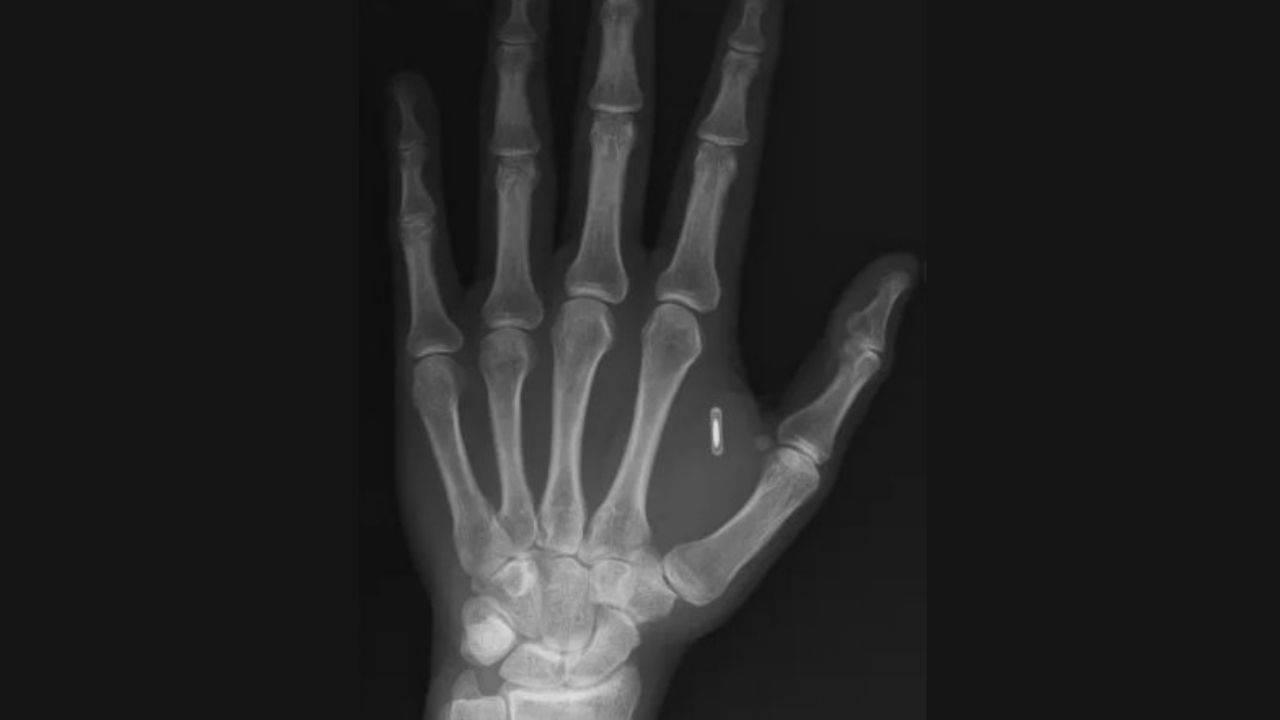

Yaşadığı durumu Facebook hesabından elinin röntgen görüntüsüyle paylaşan Wang "Şu anda kendi siberpunk distopyamı yaşıyorum, kendi vücudumdaki teknolojiye erişemiyorum ve bu tamamen benim aptallığım" diye yazdı.